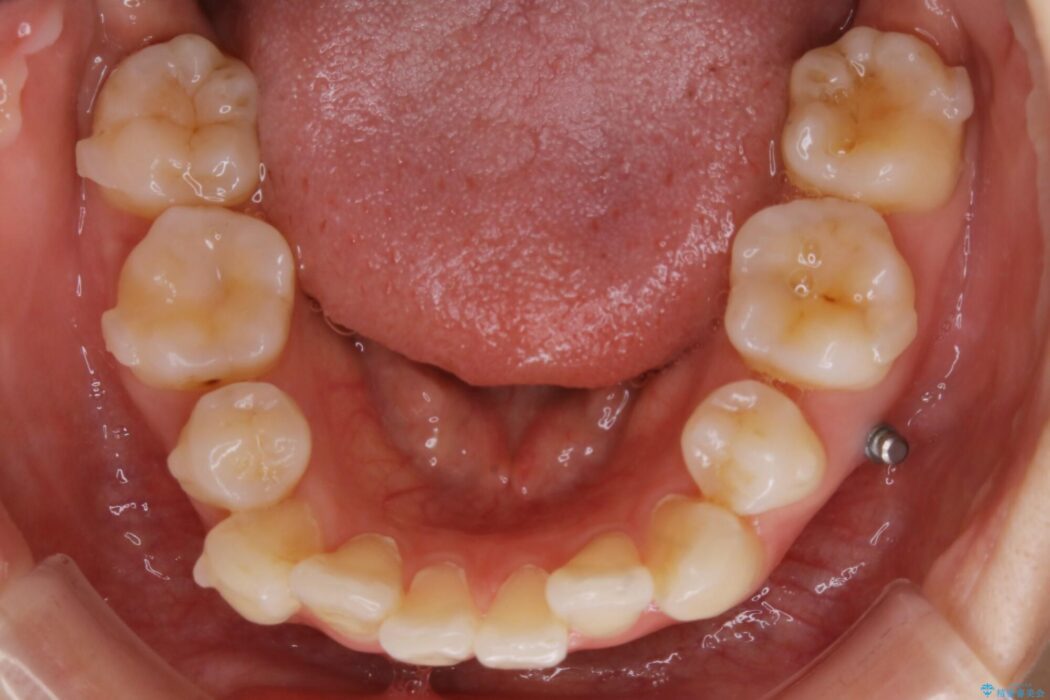

以前治療した抜歯矯正から後戻りをしてしまった歯列のがたつきを再矯正したいとのことで来院されました。

元々中学生から高校生にかけてワイヤー装置を用いた矯正治療をされた患者様でした。

大人になるにつれてライフスタイルの変化が生じ、歯が元の位置に戻らないように保定するためのリテーナーを継続使用することが難しくなったことから、歯列にがたつきが目立つようになったのでもう一度矯正治療をしたいとのご希望でした。

既に上下左右の4番目の歯が抜歯されているため、今回のケースでは非抜歯による歯の移動のみで矯正をしなければならず、難易度が高いものになりました。